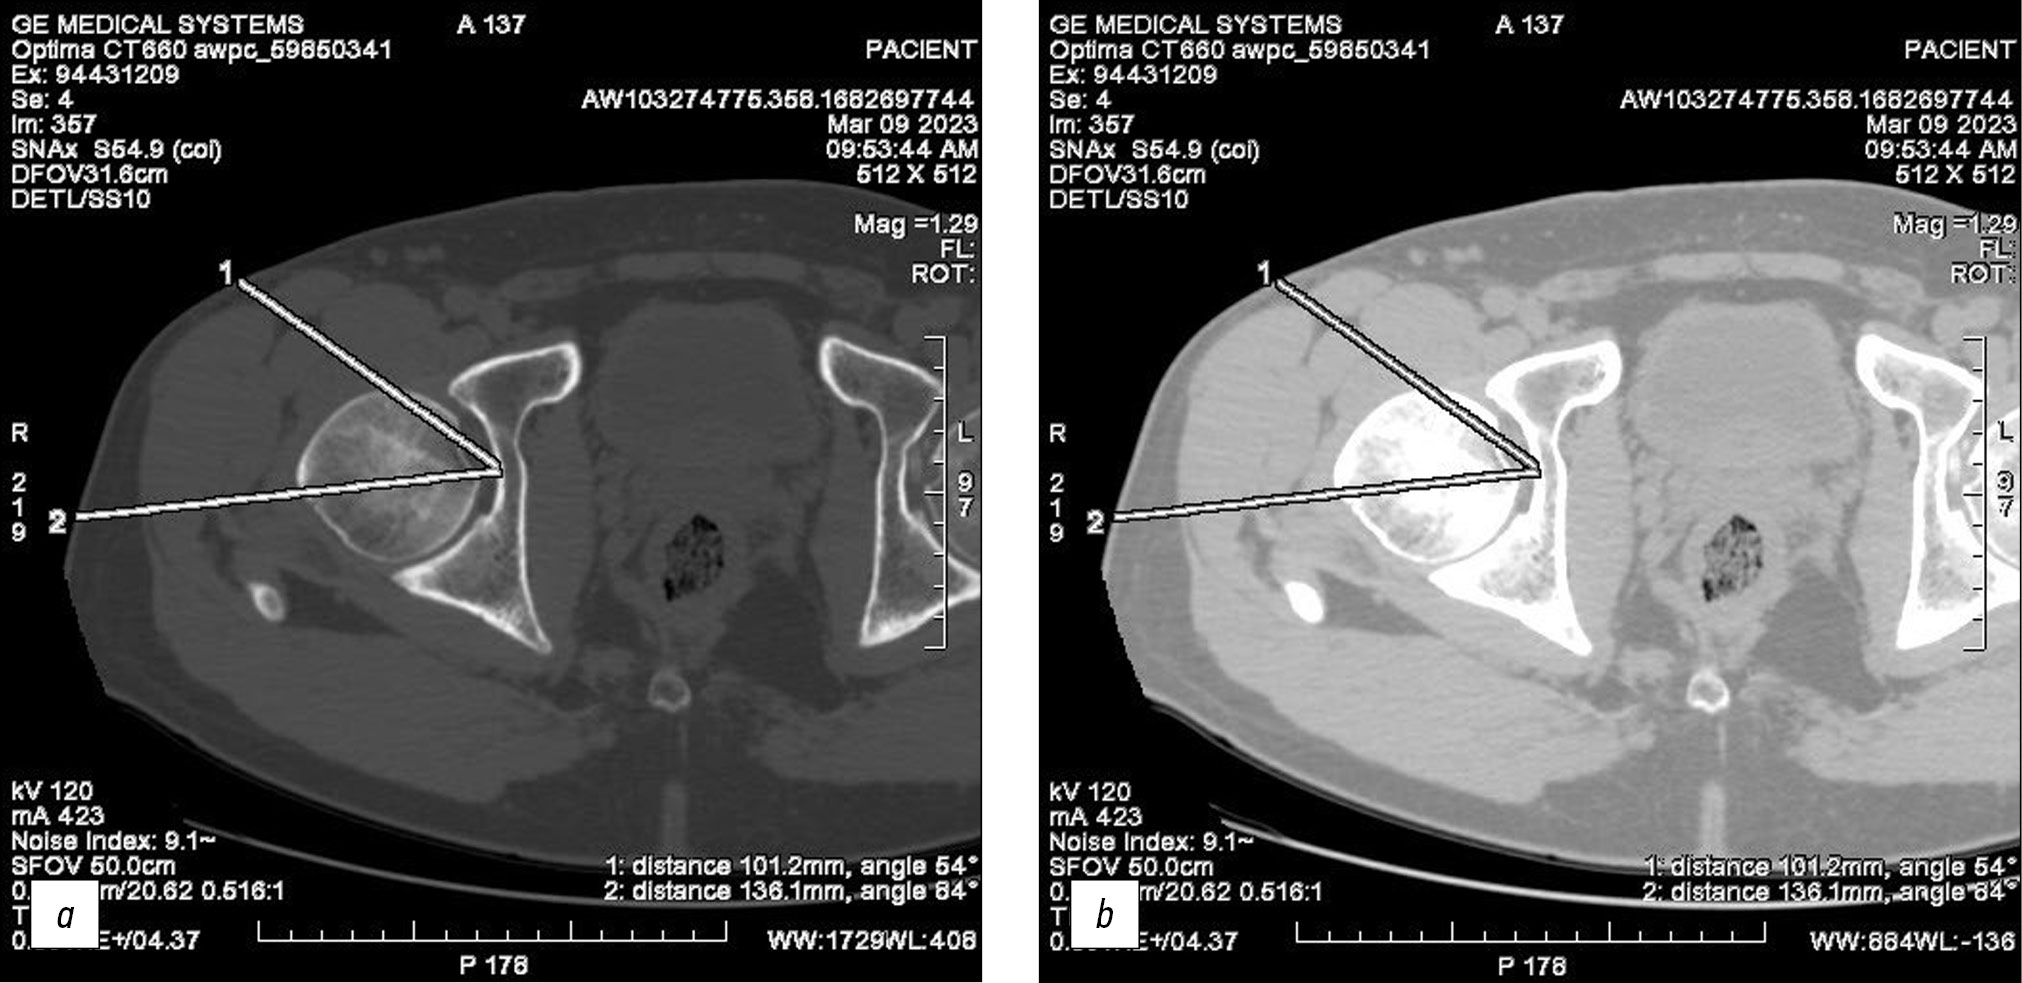

При переднем доступе к тазобедренному суставу глубина раны на 20–25% меньше, чем при доступе по Хардингу — 101 и 136 мм соответственно (рис. 9).

Рис. 9. Снимки мультиспиральной компьютерной томографии, аксиальные срезы: a — костный режим, b — мягкотканный режим, 1 — измерение глубины раны при переднем доступе, 2 — измерение глубины раны при доступе по Хардингу.

Fig. 9. Images of multislice computed tomography, axial sections: a — bone mode, b — soft tissue mode, 1 — measurement of the wound depth in the anterior approach, 2 — measurement of the wound depth in the Harding approach.